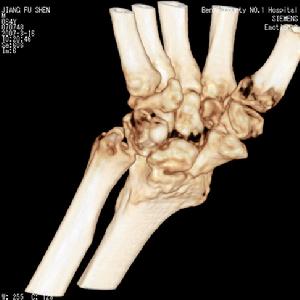

腕關節結核X線表現滑膜型早期可見腕骨小梁模糊,皮質密度變淡,輪廓不完整。晚期由於骨皮質消失及皮質下侵蝕,腕骨可變小。骨型病灶首先開始於橈骨遠端,其次為腕骨(如舟骨、大多角骨、頭狀骨及三角骨),很少繼發於尺骨。病灶常為多發,呈類圓形或不規則形骨缺損,很少有死骨。晚期關節間隙均變窄,病變嚴重者可侵及第2、3掌骨基底部,甚至可達骨幹,可伴有輕度骨質增。生及骨膜反應。病骨往往呈膨脹改變。腕骨結核常合併腱鞘結核,有時可見斑點狀鈣化。兒童的腕關節結核,患側化骨核出現較早。

腕關節結核--CT腕月、舟骨缺血性壞死骨密度增高,有時可見囊變,或呈不規則碎裂。腕關節一般無狹窄,亦無骨破壞。